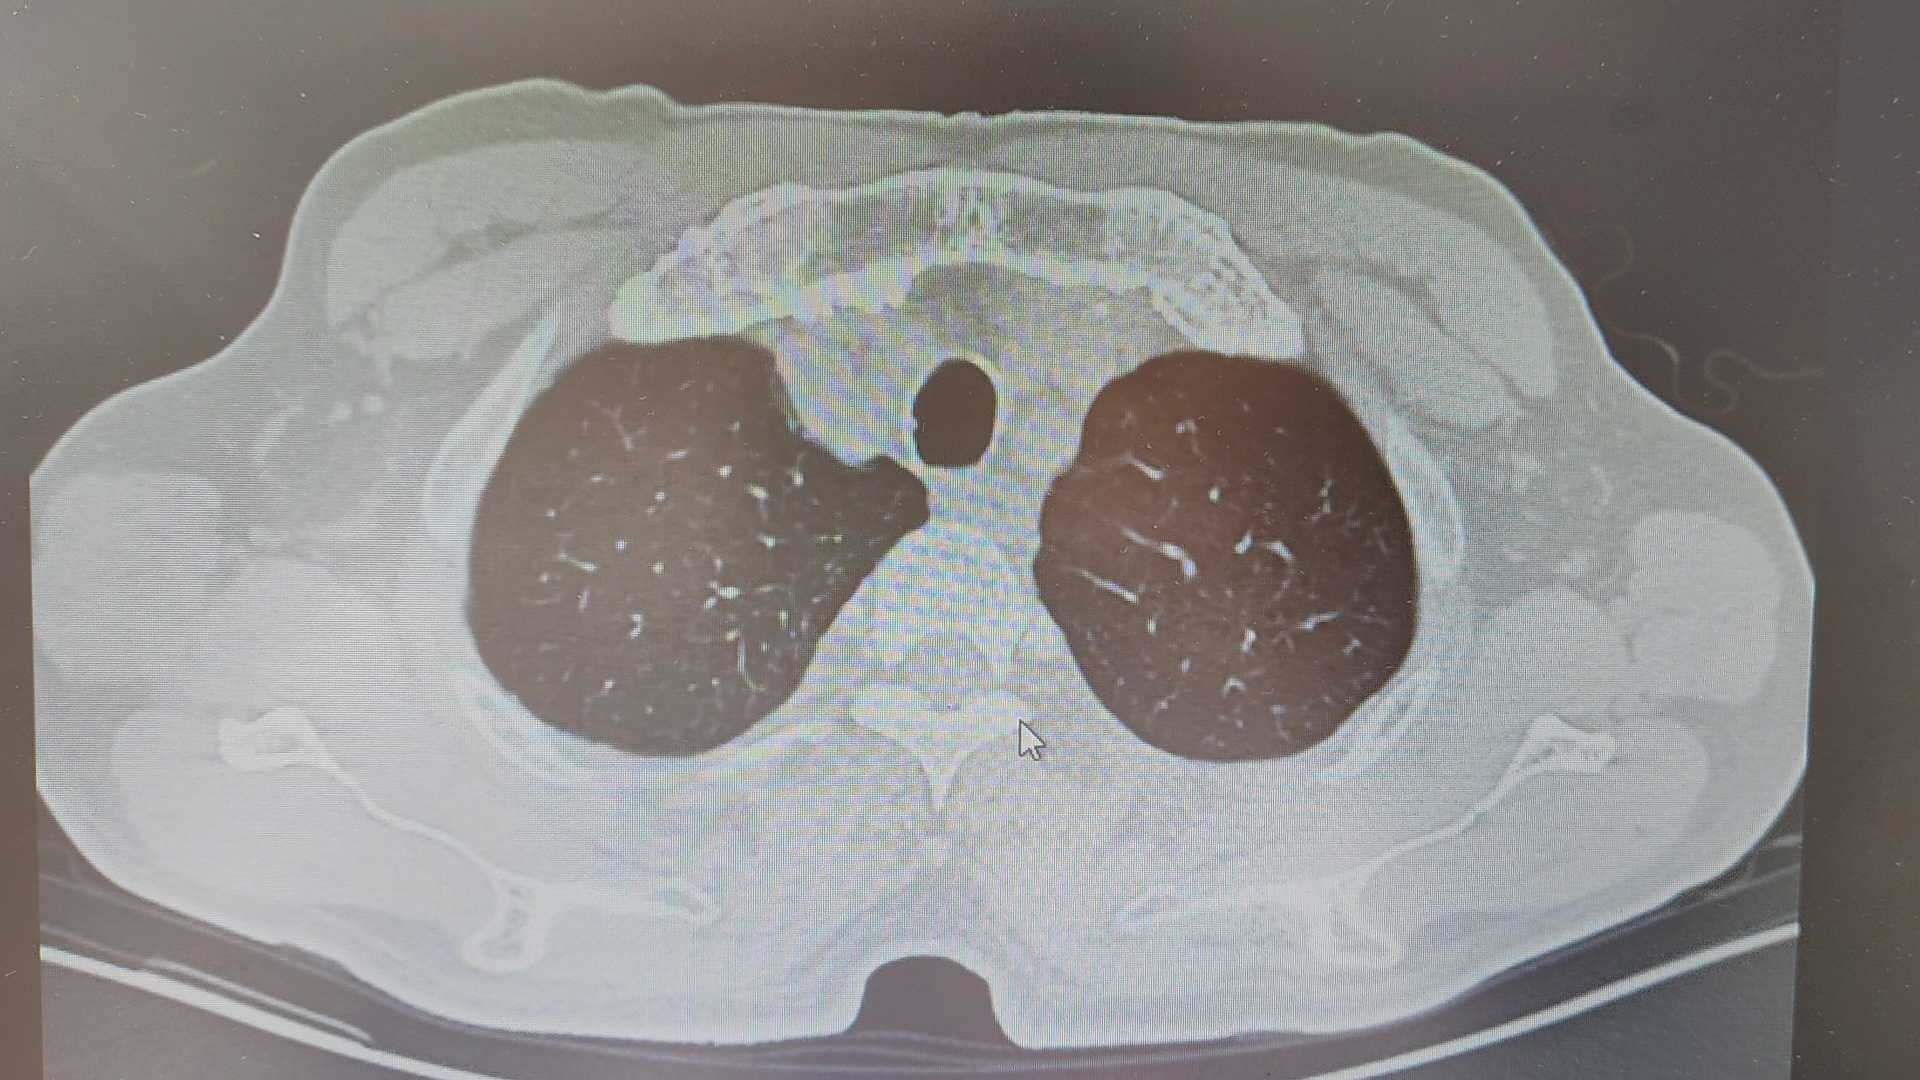

气管里是什么?

讨论气管内是什么?ct值80左右